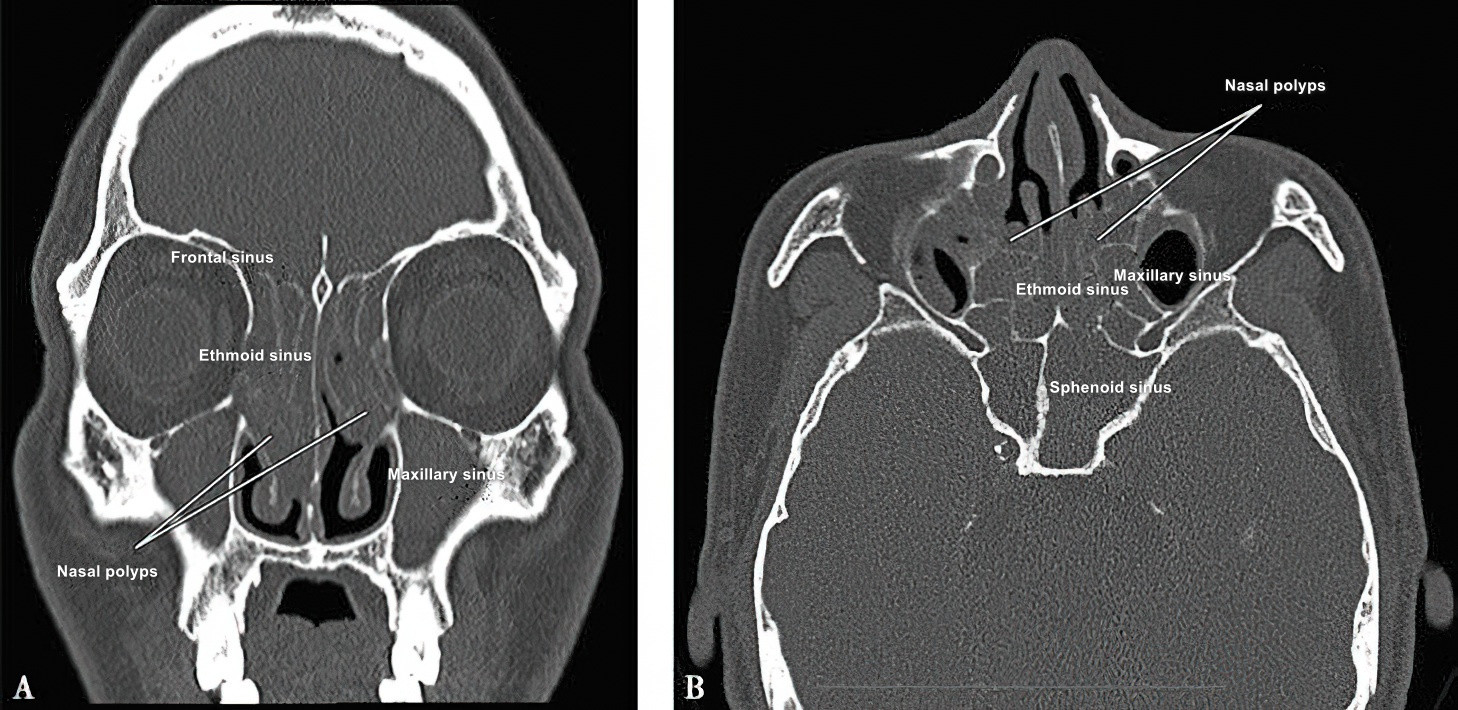

Computed tomography (CT) scanning of the paranasal sinuses is the primary imaging method but is not a mandatory diagnostic criterion. CT scans can show the extent of sinus involvement, the severity of mucosal lesions in the nasal cavity and sinuses, nasal septal deviation, and anatomical variations related to the paranasal sinuses. Certain CT features may indirectly indicate the type of inflammation present in the sinus mucosa. Magnetic resonance imaging (MRI) of the sinuses is generally not used for diagnosing CRS.

Figure 1 CT scan showing bilateral pansinusitis with nasal polyps

A. Coronal view; B. Axial view.